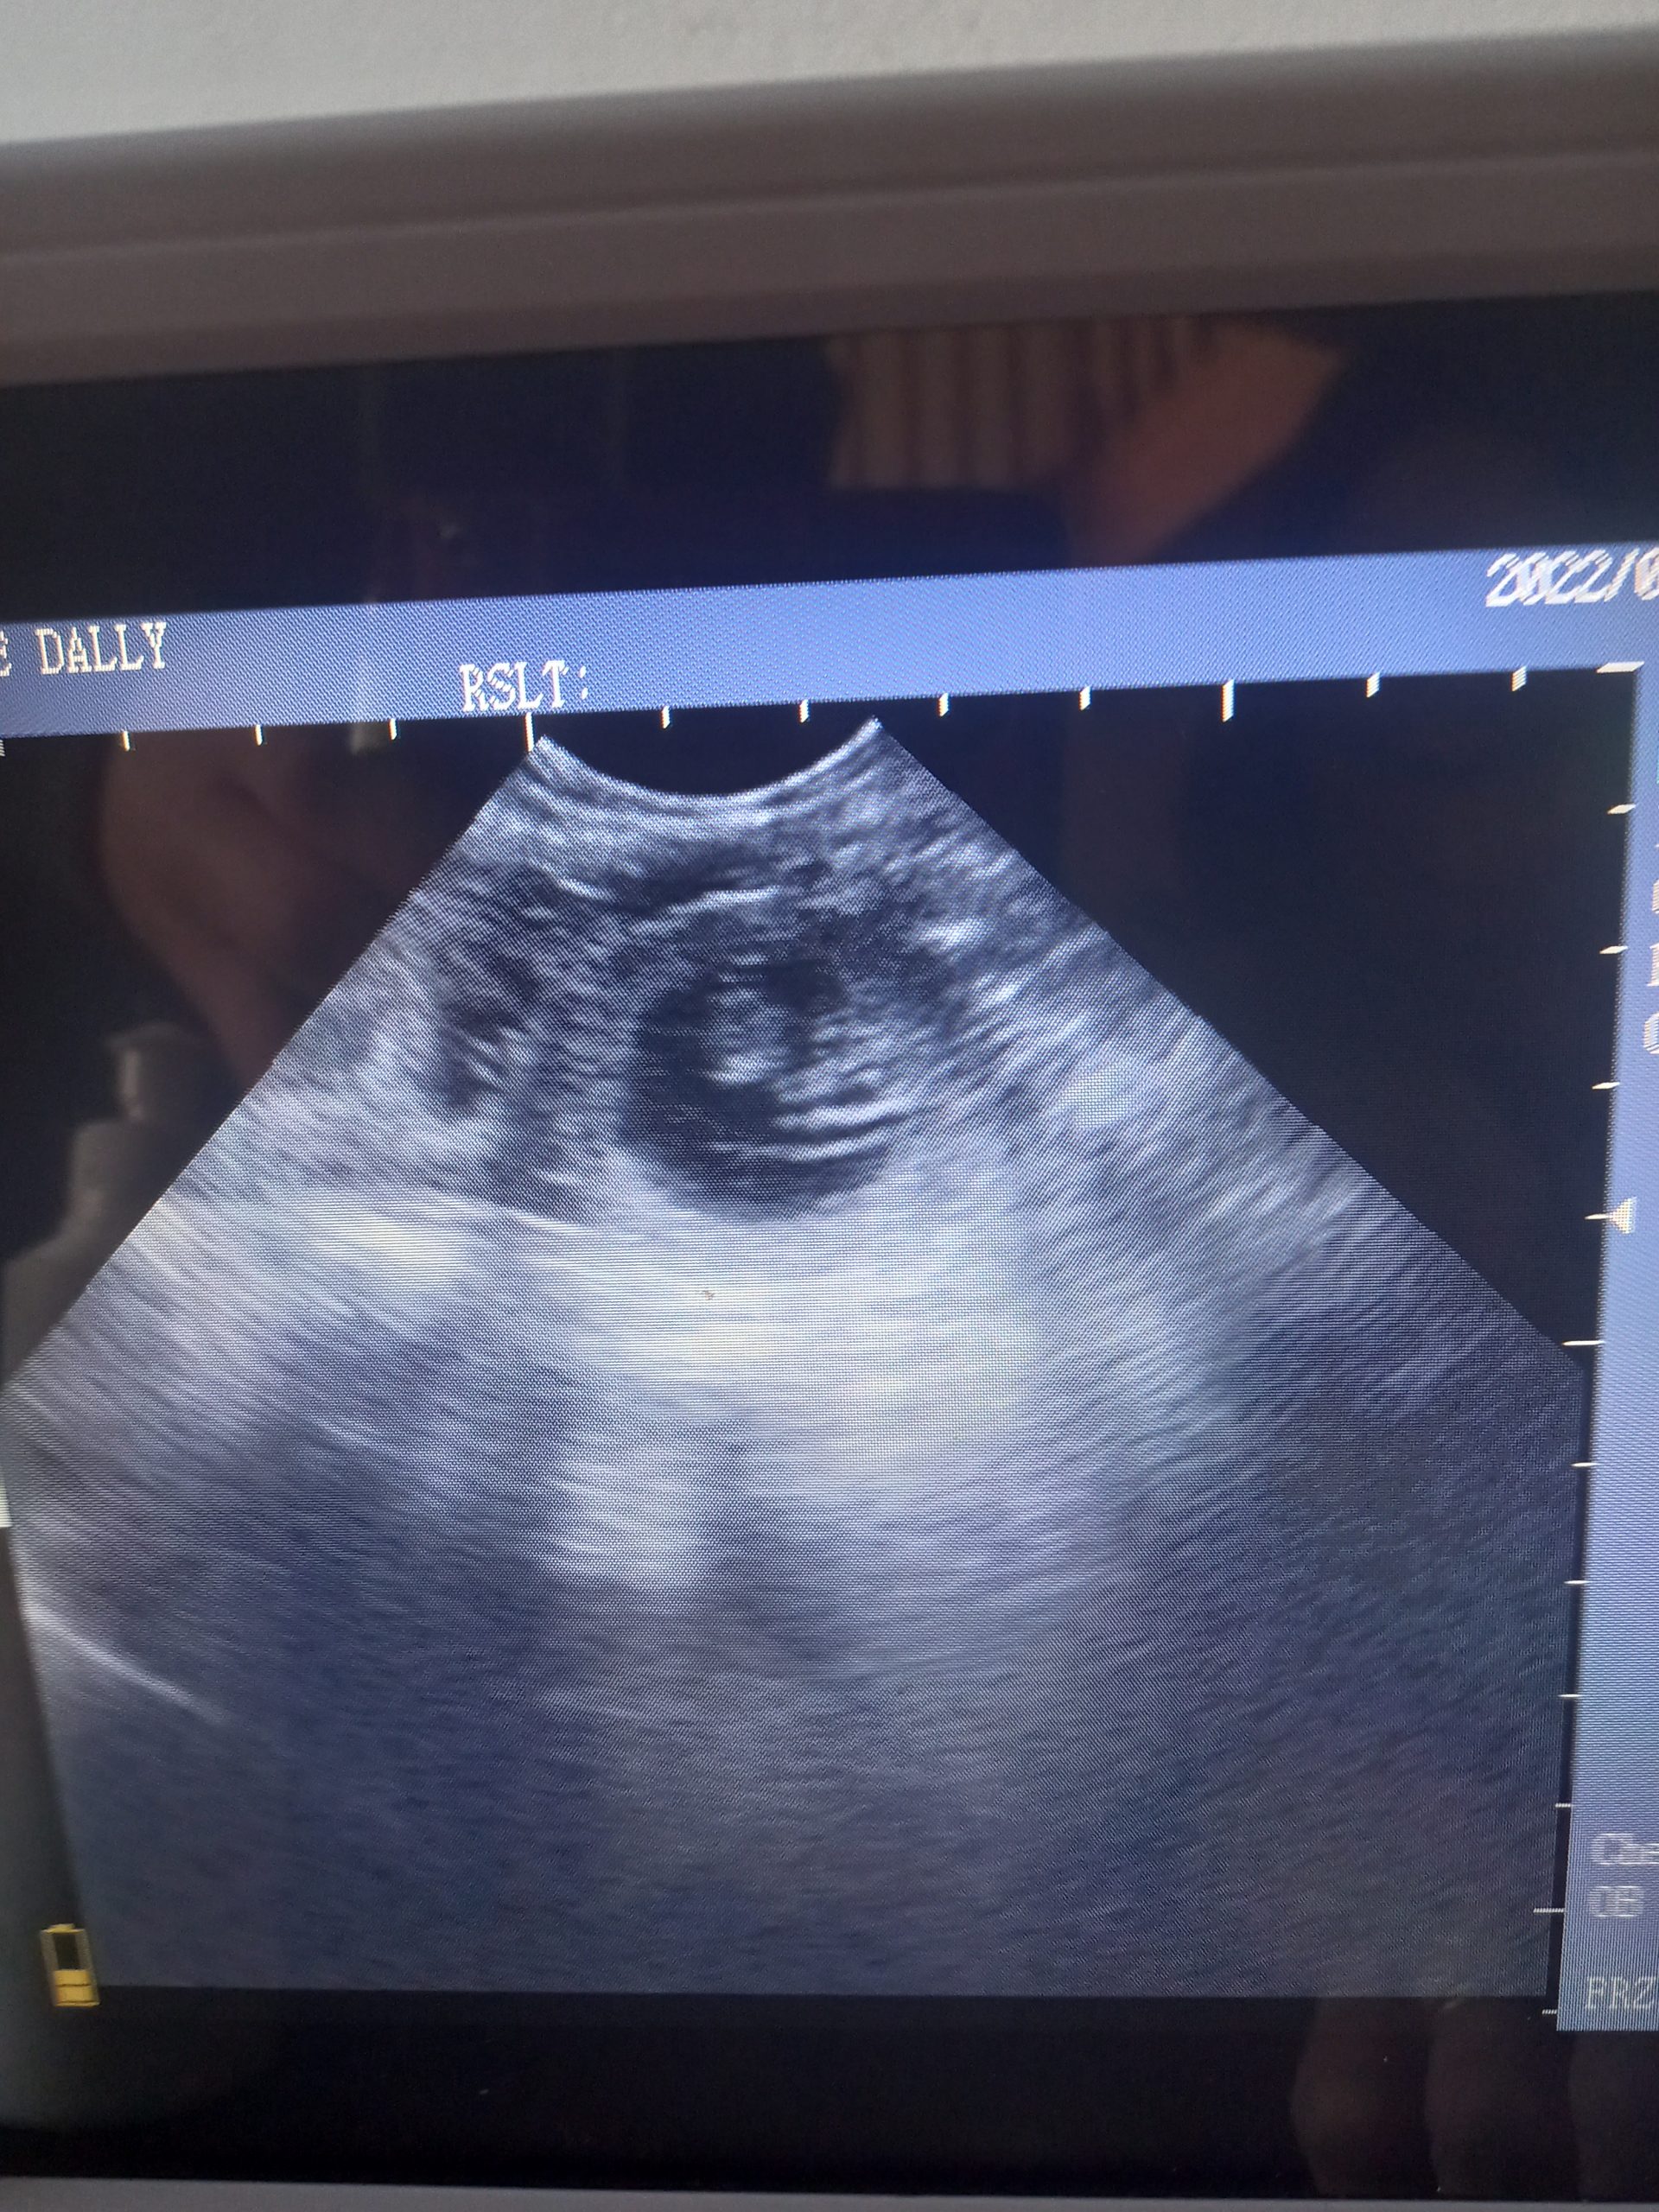

Beautiful scan of a 4yr old Labrador, confirmed multiple pups at 30days.